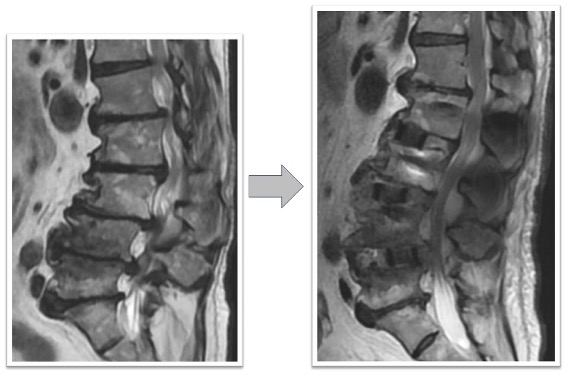

腰椎すべり症+椎間板ヘルニア(図2)

下肢痛で来院し歩行困難のため手術となりました。術前認められていたL3/4の椎間板ヘルニアがOLIFによる固定術後消失(赤丸)、またL4/5に認められていた変性すべり症による椎体のずれ、不安定性も術後は元の脊椎の並びに矯正された状態で固定されています(黄丸)。術後は症状消失し、元通り歩行可能となりました。

図2